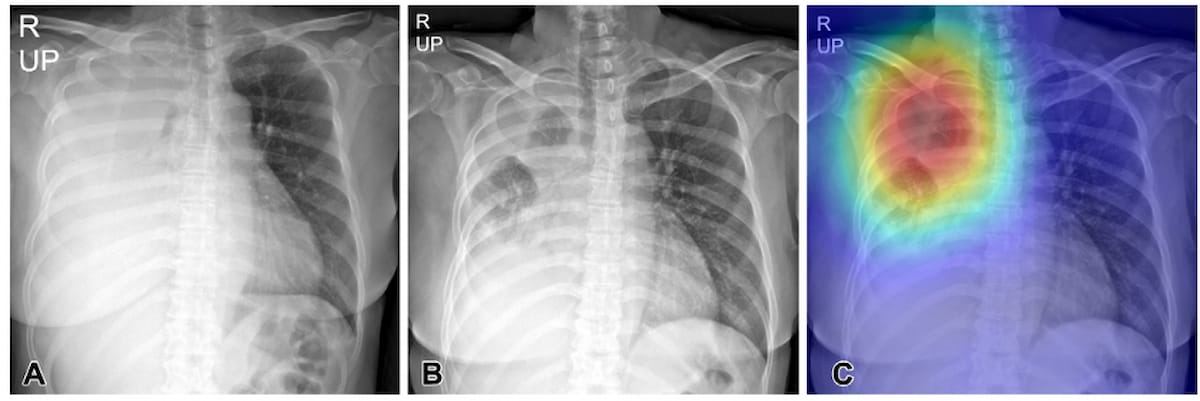

In a multicenter study examining four commercially available artificial intelligence (AI) software products for chest X-rays in over 2,000 patients, researchers found sensitivity rates ranging between 33 to 61 percent for vague airspace disease and 9 to 94 percent for small pneumothorax and pleural effusion.